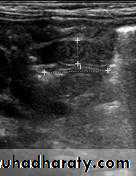

Hypertrophic pyloric stenosis refers to idiopathic thickening of gastric pyloric musculature which then results in progressive gastric outlet obstruction

In a normal situation, the pyloric muscle thickness (diame­ter of a single muscular wall on a transverse image) should normally be less than 3 mm (most accurate 3) and the length (longitudinal measurement) should not exceed 15 mm.